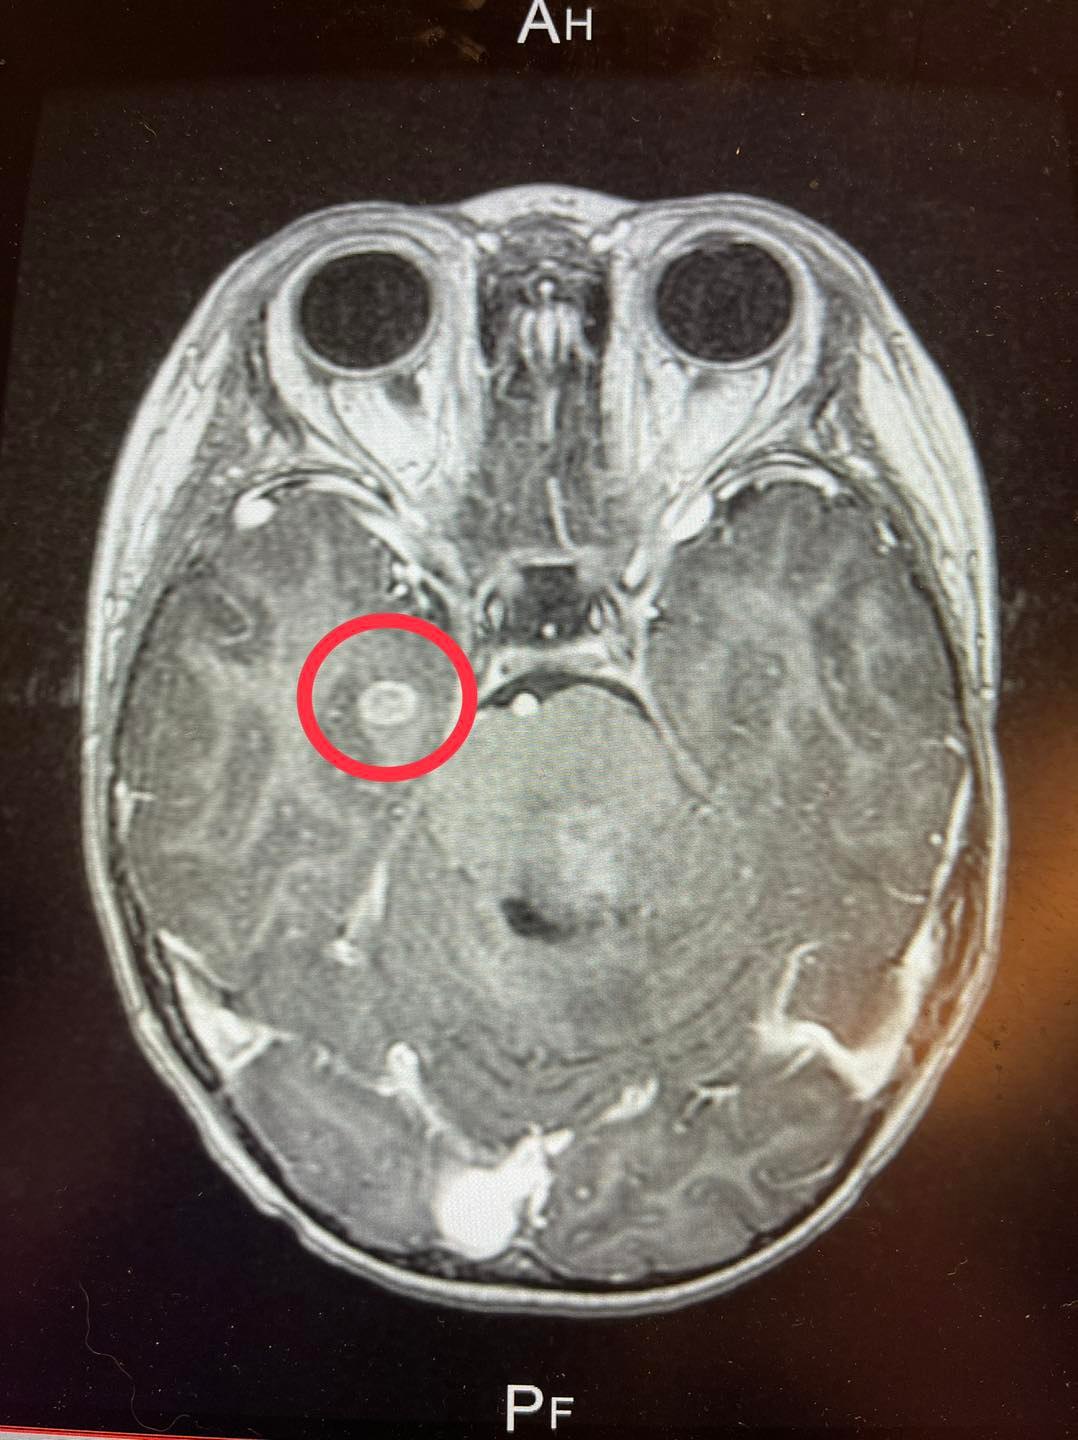

便當夫人透露,兒子晨翔剛過完4歲生日沒多久後,突然在某天將飯後吃的水果全部嘔吐出來,一開始媽媽以為只是腸胃型感冒,但後來出現走路歪斜、頭歪右邊等症狀,就連笑容也只有半邊臉有反應。媽媽驚覺不對勁,馬上送兒子到醫院檢查,診斷發現兒子晨翔的腦幹有個約6厘米大的陰影,經影像分析結果確診是罕見疾病「DIPG腦癌」。

瀰漫性內生性腦橋腦膠質瘤(DIPG)是一種具有破壞性,侵襲性的兒童腦腫瘤。它出現在腦橋中,腦幹涉及關鍵的身體功能。發病年齡平均為5-9歲佔中樞神經系統腫瘤的一成。